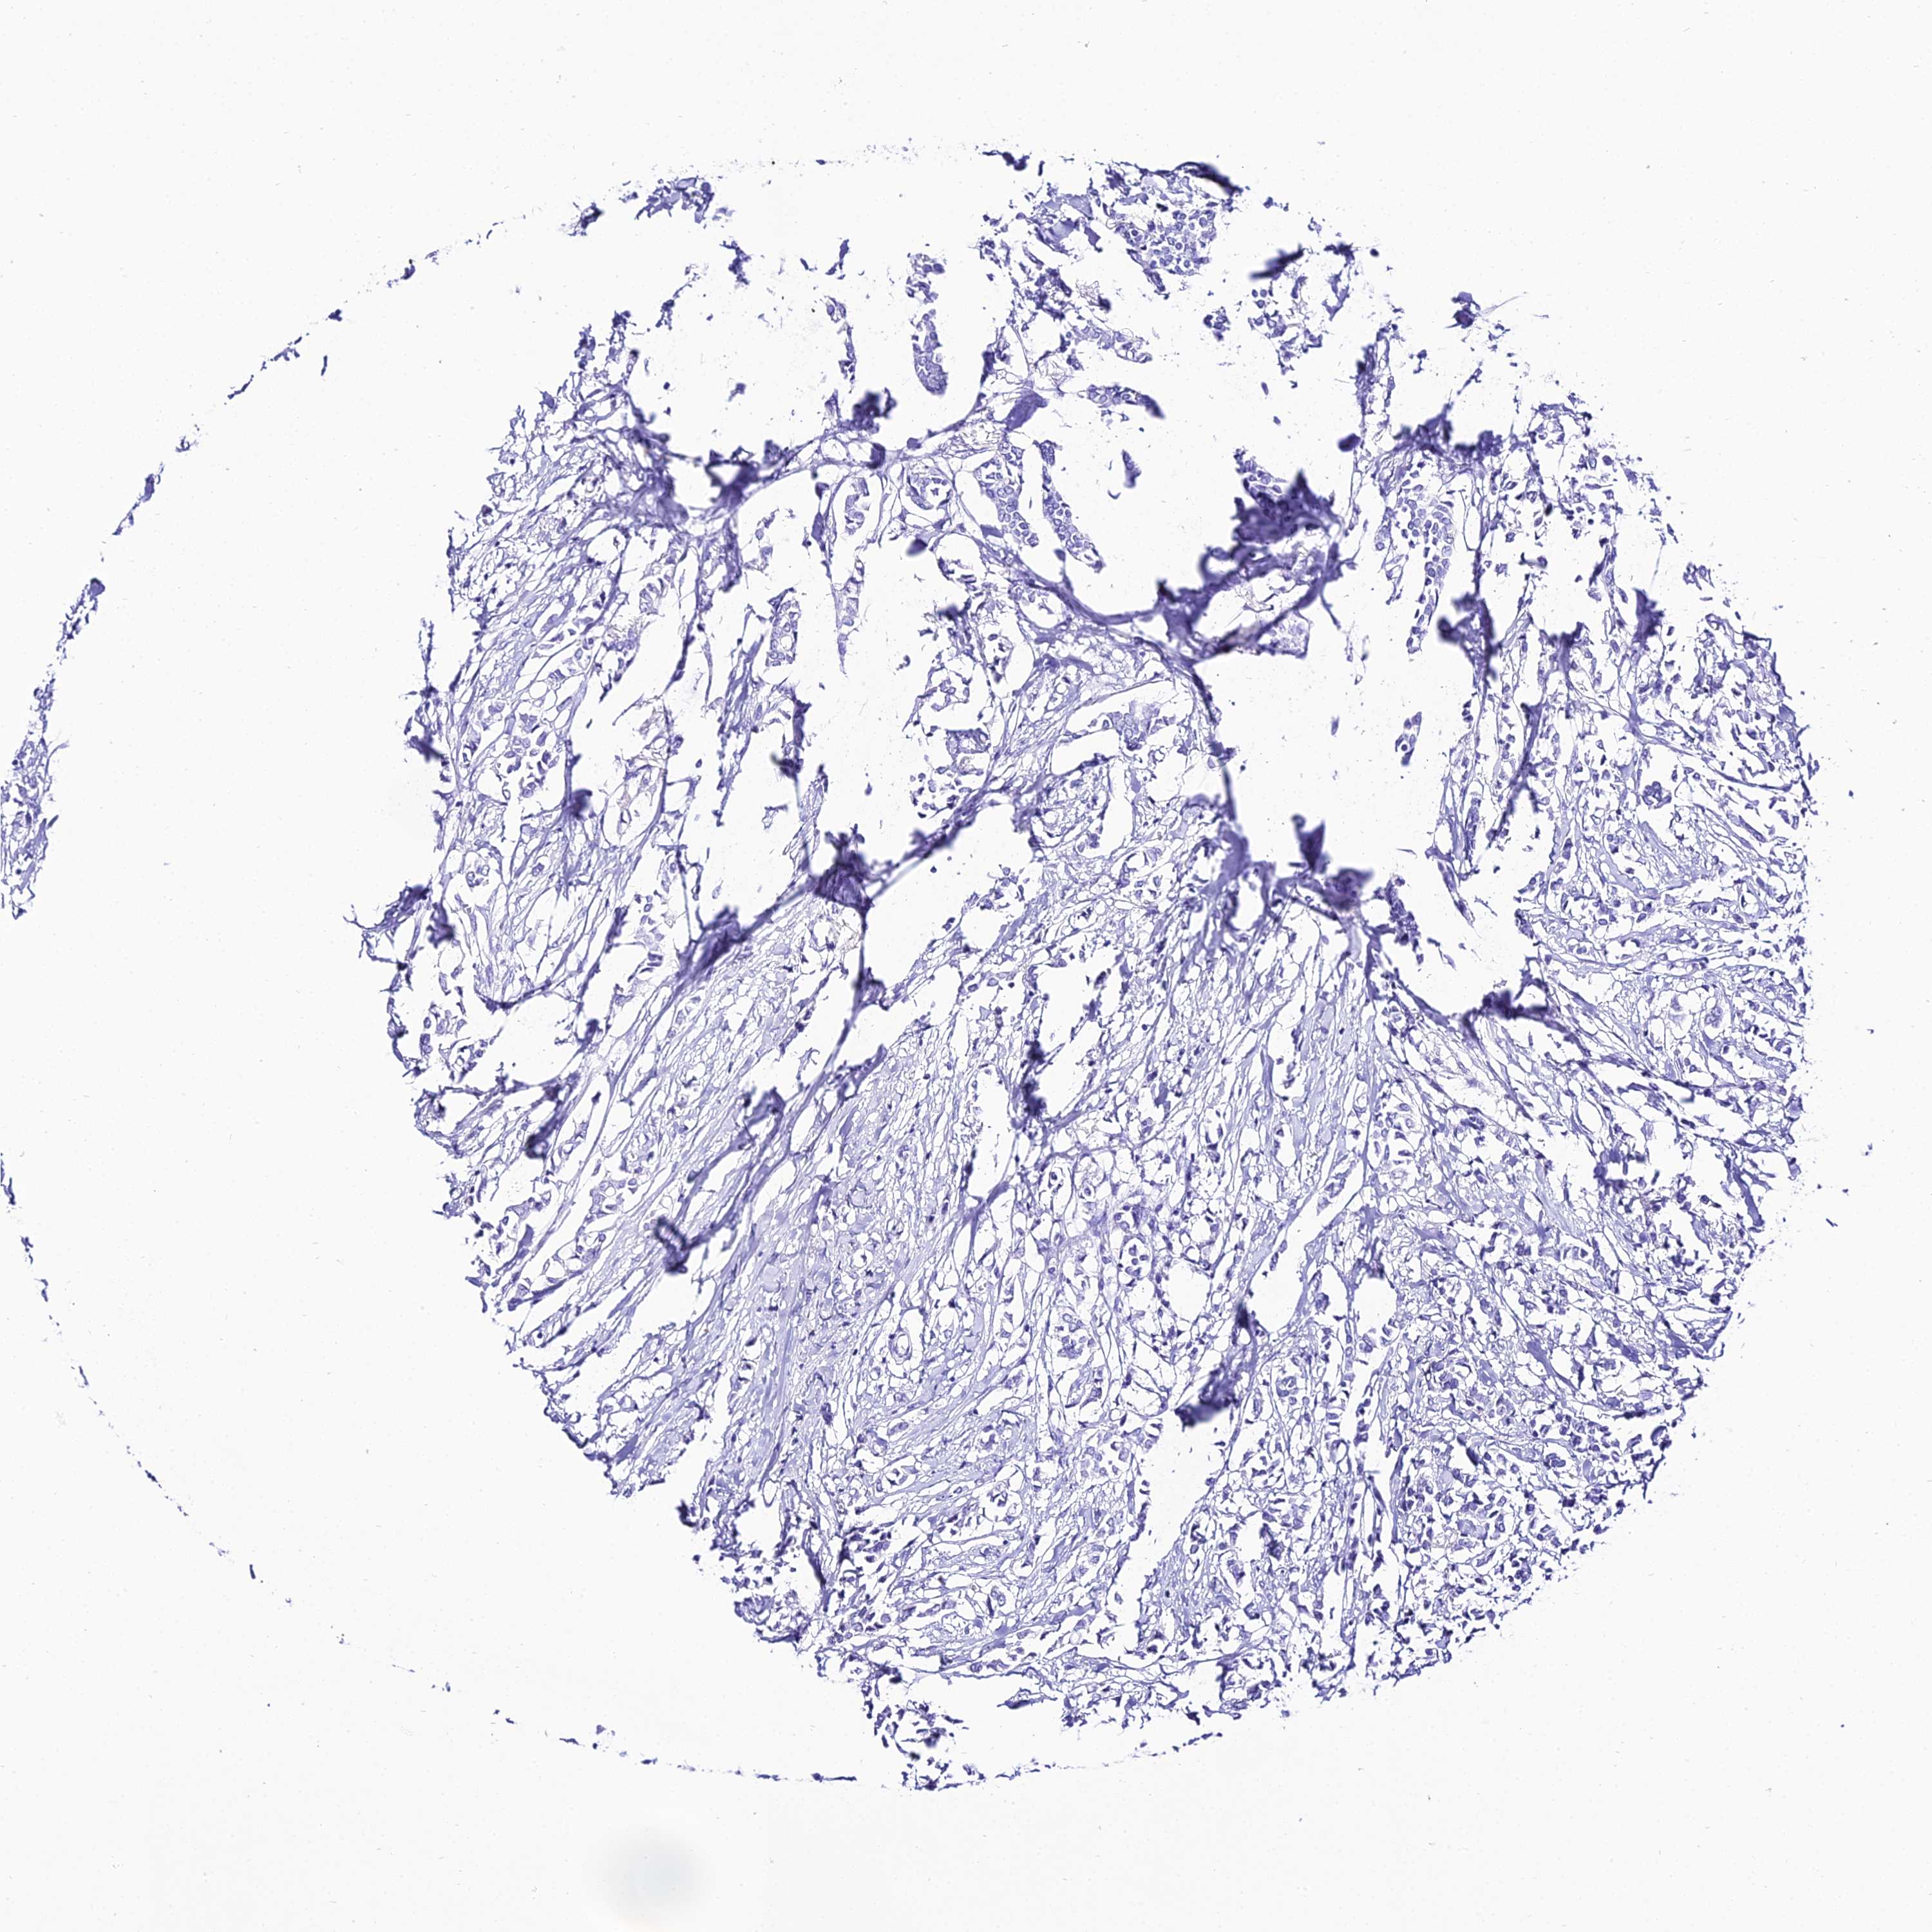

CANCER BREAST CANCER Show tissue menu

Breast cancer

Human cancer

TRMT44 is not prognostic in Breast Invasive Carcinoma (TCGA)